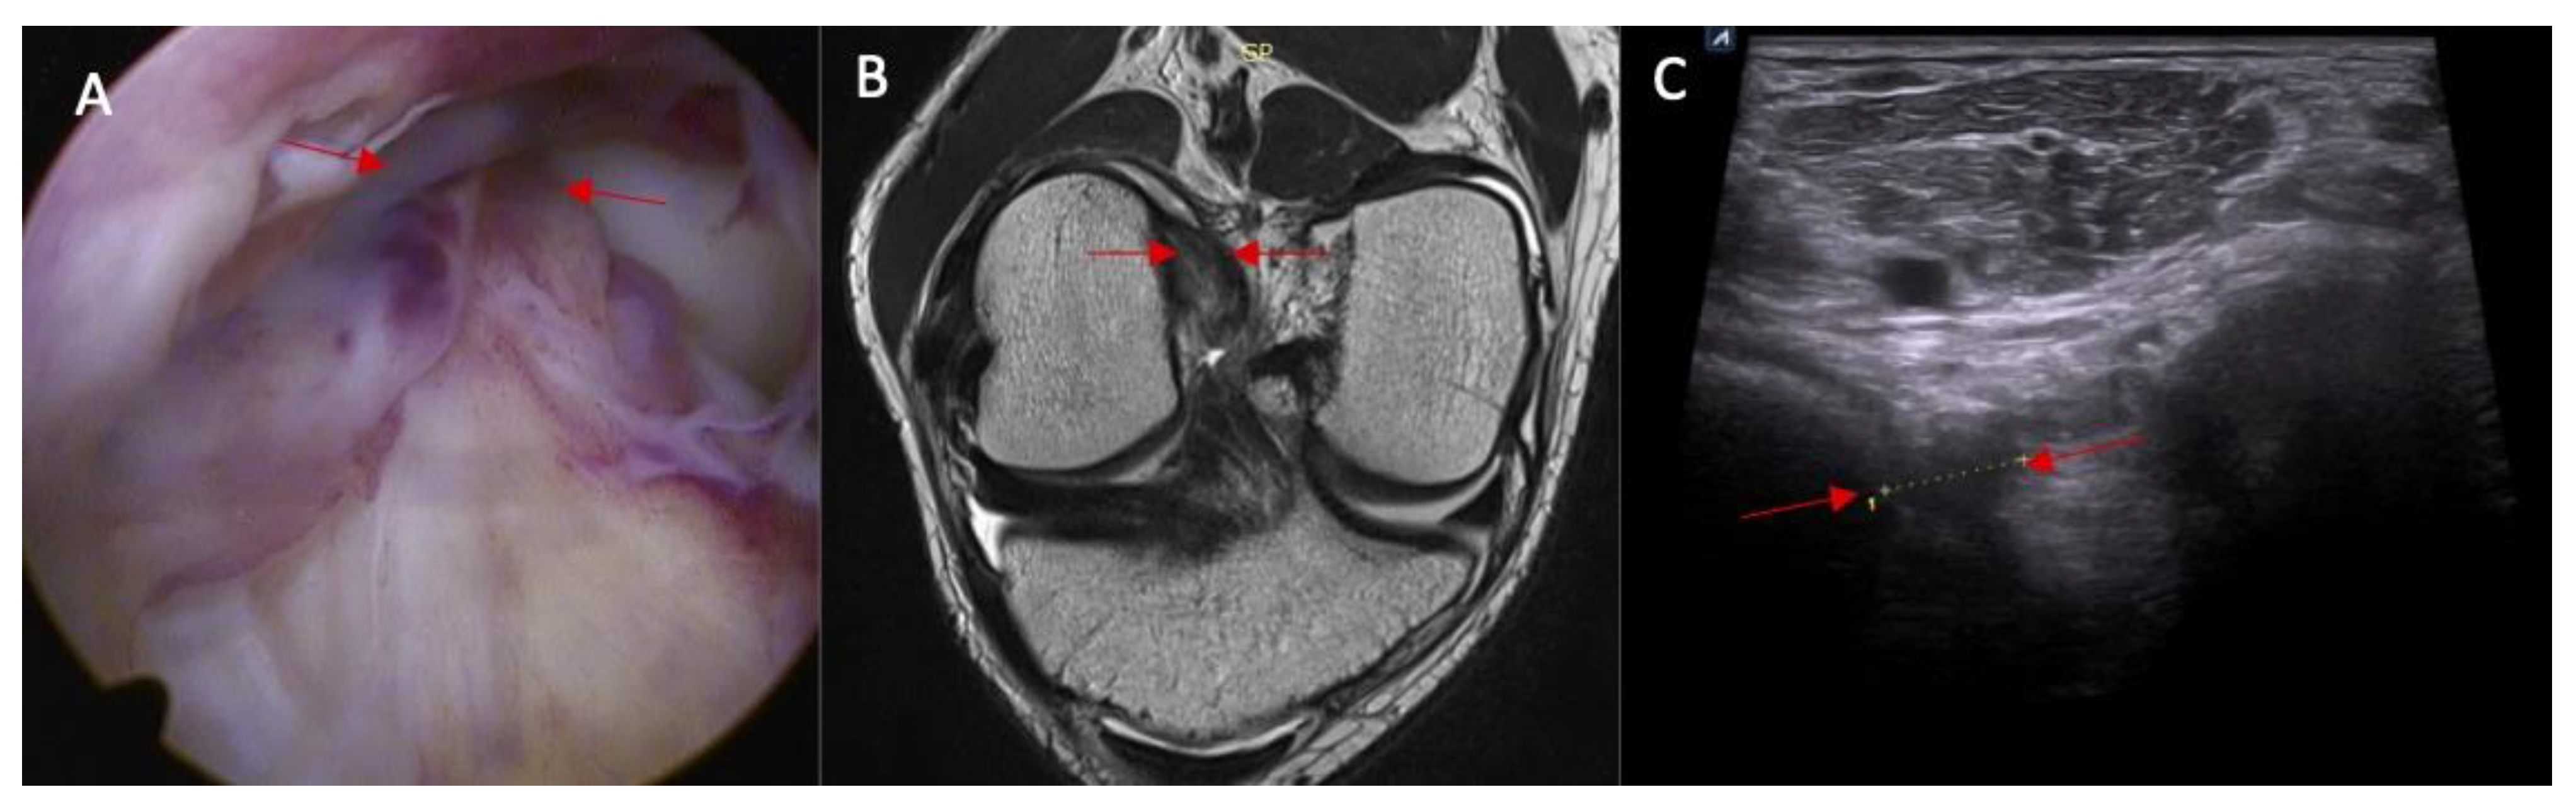

Swelling of the ACL/PCL on ultrasound was more common in patients with an ACL injury than in those without an ACL injury (88% vs. 0%, respectively, and p < 0.0001) (Figure 6 and Figure 7). OR = incalculable.

Figure 7.

(A) ACL tear confirmed in arthroscopy view. Swelling of the ACL/PCL compartment with change of the morphology of the posterior joint capsule complex in (marked with red arrows) MRI view (B) and ultrasound view (C).